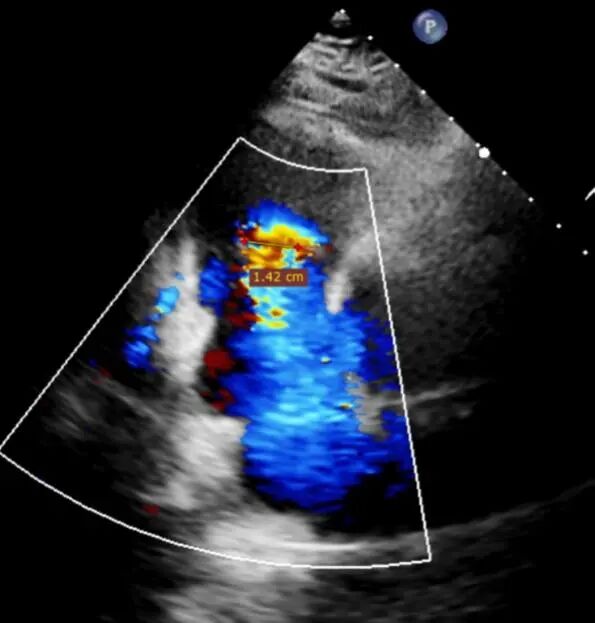

Preoperative echocardiographic evaluation: severe tricuspid regurgitation (grade 5+).

1. Preoperative baseline regurgitation

Regurgitation assessment: Regurgitation severity reduced from preoperative 5+ to 1+.